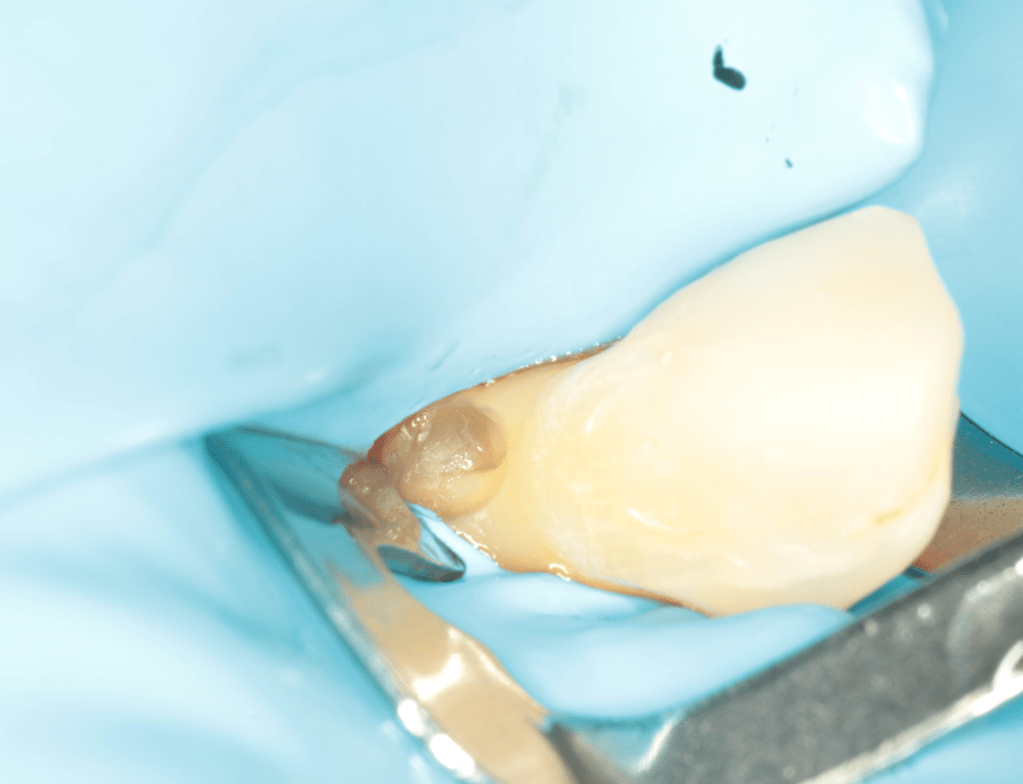

REIMPLANTES

Intencional por dificil acceso coronal y quirúrgico

Reinplante por fracaso de tratamiento

Reimplante, istmo apical, curación cortical palatina 1 año